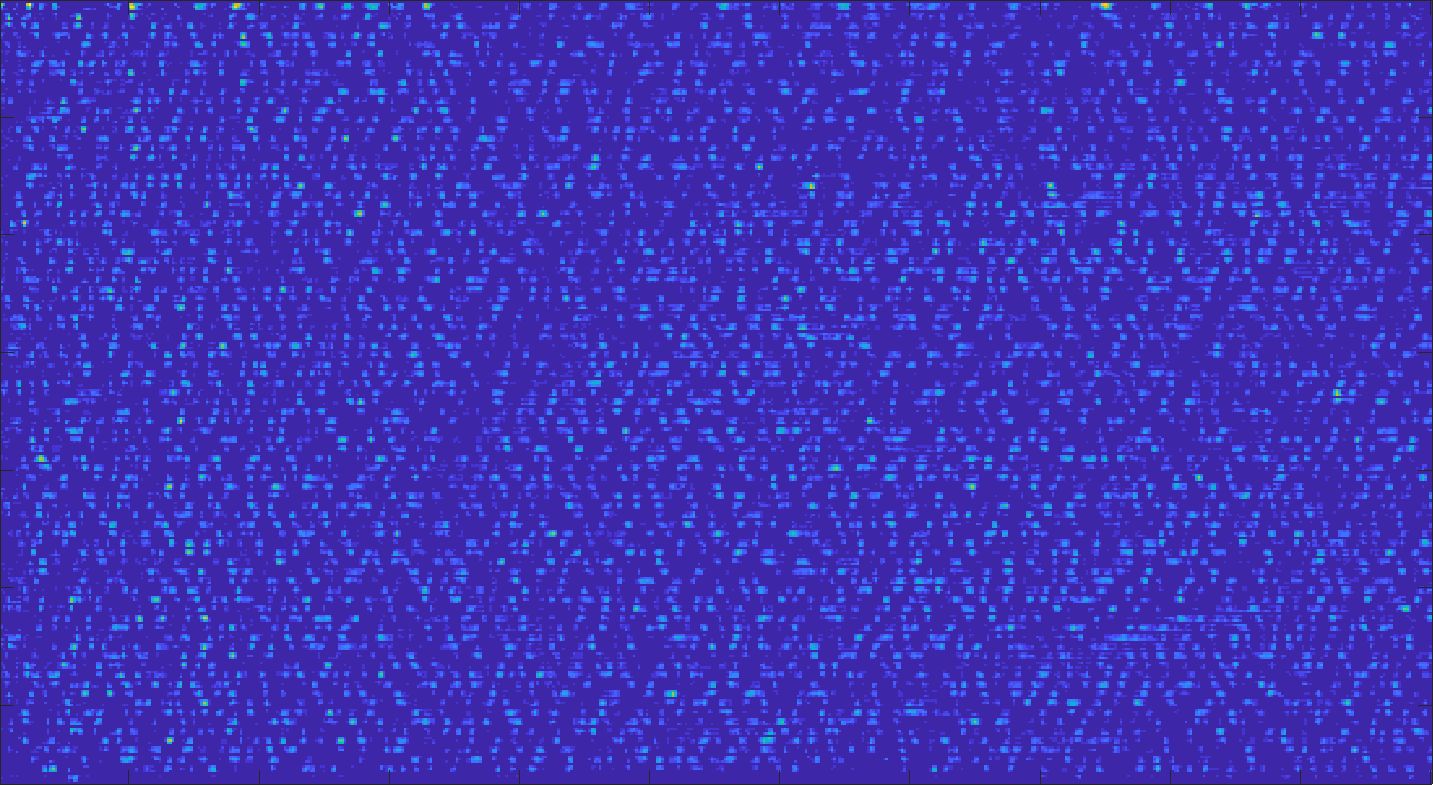

We train each learning-based network (custom-WDSR) with 1.5K images, where the input is the outcome of the selected up-sampling method (i.e., Cubic convolution), and the target is the original high-resolution image. Indeed, input and target images have the same resolution, as the reconstruction of the missing lines has been already performed by Cubic convolution. Figs. 3, 4, and 5 show the results of the network prediction, compared with the input and the target images. Target images correspond to spatial high-resolution images; input images are the outcome of the up-sampling interpolation, which is applied to spatial low-resolution images (i.e., the down-sampling along the lateral direction of high-resolution images); prediction images represent the output of the neural network.

Our framework visually improves the results, in terms of blurring and artefacts. This result is more evident in the magnification of the ear of the foetus (Fig. 3), the mitral valve (Fig. 4), and the mass edges (Fig. 5). Fig. 6 shows the error image of the three anatomical districts with both 2X and 4X up-sampling factors, with the maximum error in the scale . The error is more evident in the contours of the anatomical structures; moreover, the abdominal district shows a smaller error than the cardiac and obstetric ones. We underline that the view for each image is scaled to its maximum, to improve the visualisation of the error.

The analysis of the absolute value of the difference between the input and the prediction of the network (Fig. 9) shows that the alteration of our prediction to the pixel values ranges from 0 to a maximum absolute value of 20, mainly located on the edges of the anatomical structures; furthermore, the black uniform areas are less affected by the prediction. In terms of the distance between the input and the prediction, we do not observe a significant difference among anatomical districts and between 2X and 4X up-sampling.